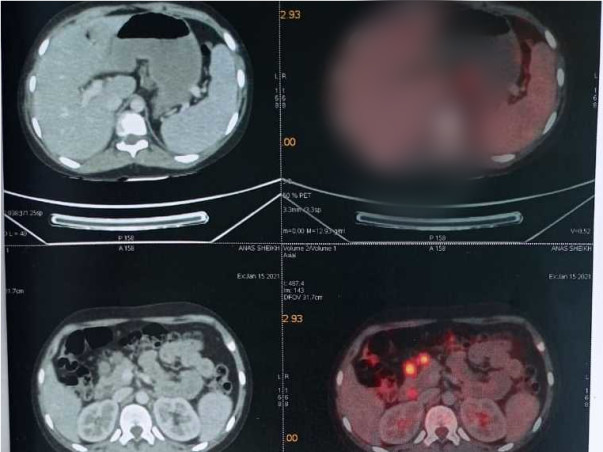

To make a living, his father works as an Auto Driver. Anas Sheikh is suffering from lymphoma cancer for the Past 5 Years.